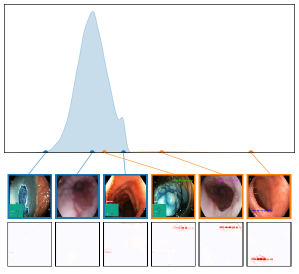

We further plot the distribution of CAV-based bias scores for biased and clean samples for the real-world artifacts ruler (ISIC2019) and pacemaker (CheXpert) in Fig. 8. We compute bias scores using the best performing CAV per artifact and use latent activations after the residual block of the ResNet50 model for ruler, and the convolutional layer of the VGG16 model for pacemaker. We show samples corresponding to the bias score in the top-1 and -99 percentiles of each set. Samples near the decision boundary are particularly interesting, as they may arise from labeling errors. Both examples demonstrate the retrieval of unlabeled artifact samples. The distributions of bias scores for additional artifacts are shown in Appendix A.6.2.